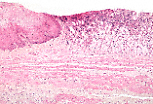

Tube digestif